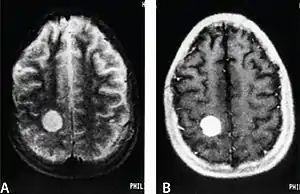

MRI of a cardiac angiosarcoma that has metastasised to the brain.

Primary cardiac angiosarcoma is an angiosarcoma that arises in the heart. Despite being very rare they are the most common malignant primary heart tumor with 10–25%[9][3] of cases being angiosarcomas. Symptoms may include shortness of breath, chest pain (46%[9]), hypotension and syncope. Superior vena cava syndrome is reportedly a complication of cardiac angiosarcoma.[7] Due to the non-specificity of symptoms and rarity of the disease it is often missed by doctors and initial diagnosis may be delayed. A 2012 study reported that 56% of patients presented with pericardial effusion with or without cardiac tamponade.[9] The most common finding on imaging is cardiomegaly. Prognosis is generally very poor with a mean survival rate of three months to four years following diagnosis.[7] Metastasis at time of diagnosis is common.[9]